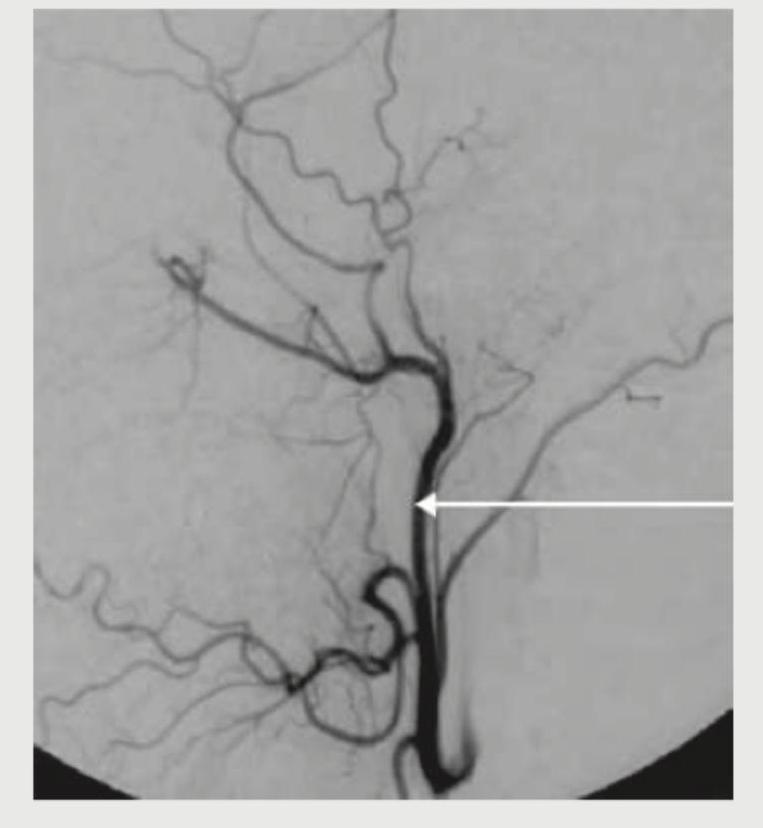

What is the name of the marked blood vessel, which is a branch of external carotid artery?

Explanation: ***Correct: Lingual artery*** - The image shows a vessel branching off the anterior aspect of the **external carotid artery** and extending towards the tongue region, which is characteristic of the **lingual artery**. - This artery typically arises at the level of the **greater horn of the hyoid bone** and supplies the **tongue** and floor of the mouth. - The anterior projection and course towards the tongue region are key identifying features. *Incorrect: Superior thyroid artery* - The superior thyroid artery typically branches off the **external carotid artery** more inferiorly, often near its origin, and descends to supply the **thyroid gland**. - This vessel, in contrast, is marked higher up and projects anteriorly towards the tongue, not inferiorly towards the thyroid. *Incorrect: Ascending pharyngeal artery* - The **ascending pharyngeal artery** usually arises from the medial or posterior aspect of the external carotid artery as a small, slender branch. - It ascends vertically to supply the **pharynx**, prevertebral muscles, and middle ear, not showing the anterior horizontal course seen in the marked vessel. *Incorrect: Maxillary artery* - The maxillary artery is a terminal branch of the **external carotid artery** that originates behind the neck of the mandible, deep to the parotid gland at a higher level. - It has a complex course with many branches supplying deep structures of the face, but its origin is much more posterior and superior than the marked vessel.